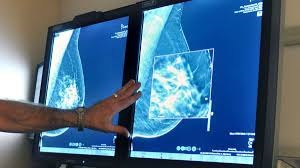

دکتر سعید اسلامی در گفتگو با وبدا، اظهار کرد: عموماً وقتی بیمار با یک علامت به رادیولوژیست مراجعه میکند و جای خاصی از بدن او بروزی از بیماری دارد، رادیولوژیست دقیقاً همان جا را بررسی میکند و کار قطعاً راحتتر است، اما وقتی غربالگری هدف ما است، رادیولوژیست باید تمام قسمتهای بافت و از جمله بافت پستان را بررسی کند تا نهایتاً به عارضه احتمالی برسد، بنابراین فرایندی که میتواند با یک علامت، ۱۰ دقیقه طول بکشد، در غربالگری ممکن است تا حدود یک ساعت هم به طول بیانجامد و لذا وقت و انرژی زیادی برای این کار نیاز است. اما یک راه جایگزین آن است که ما فرایند غربالگری را هوشمندسازی کنیم؛ یعنی از پردازش تصویر استفاده کنیم و به طور خودکار تودههای آسیب رسان را در پستان پیدا و در مرحله بعد رادیولوژیست آن را بررسی و یا حداقل به رادیولوژیست کمک بشود، این سیستم تصمیم یار میتواند زمان تشخیص را از یک ساعت به ۱۰ دقیقه کاهش دهد. در واقع سیستمهای تصمیم یار هوشمند مجهز شده به هوش مصنوعی هستند و پس از تصویر اسکن محلهای غیر عادی داخل توده پستان را علامت گذاری میکنند و رادیولوژیست آن محلها را بررسی و حتی ممکن است اعلام کنند که فرد سالم است و مشکلی ندارد.

وی در ادامه با بیان اینکه غربالگری پستان بسته به شرایط و منابعی که کشورها دارند میتواند متفاوت انجام شود، افزود: در مجموع، فرایند غربالگری به این نحو انجام میشود که ابتدا برای بانوان ماموگرافی انجام می گردد ( ماموگرافی تصویر اشعه ایکس است که از پستان گرفته میشود با دوزه پایین اشعه ایکس و عوارض آن خیلی محدود است) که بهترین روش تشخیص اولیه است و بعد تصاویر ماموگرافی توسط رادیولوژیست خوانده میشود و اگر چالشی وجود داشته باشد، این چالش گزارش شده و برای مراحل بعدی بیمار به پزشک ارجاع میشود.